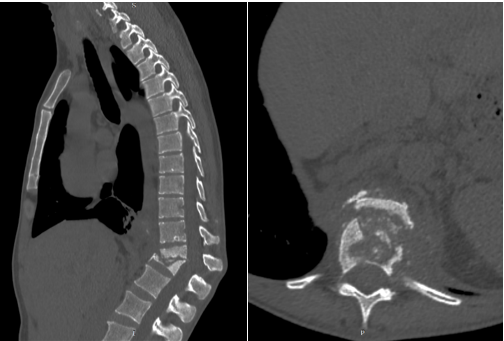

Предоперационное микробиологическое исследование включало забор крови для гемокультуры, в которой был верифицирован золотистый стафилококк. Дополнительно проведена биопсия деструктивного очага под контролем КТ, что подтвердило наличие неспецифического гнойного процесса (рис. 1). По результатам лабораторных анализов выявлены признаки системной воспалительной реакции - лейкоцитоз и повышение уровня С-реактивного белка.

Рис. 1. Компьютерная томография (сагиттальная и аксиальная проекции). Определяется деструктивный процесс тел Tp2–L1 (Pola C4) Составлено авторами по результатам данного исследования.